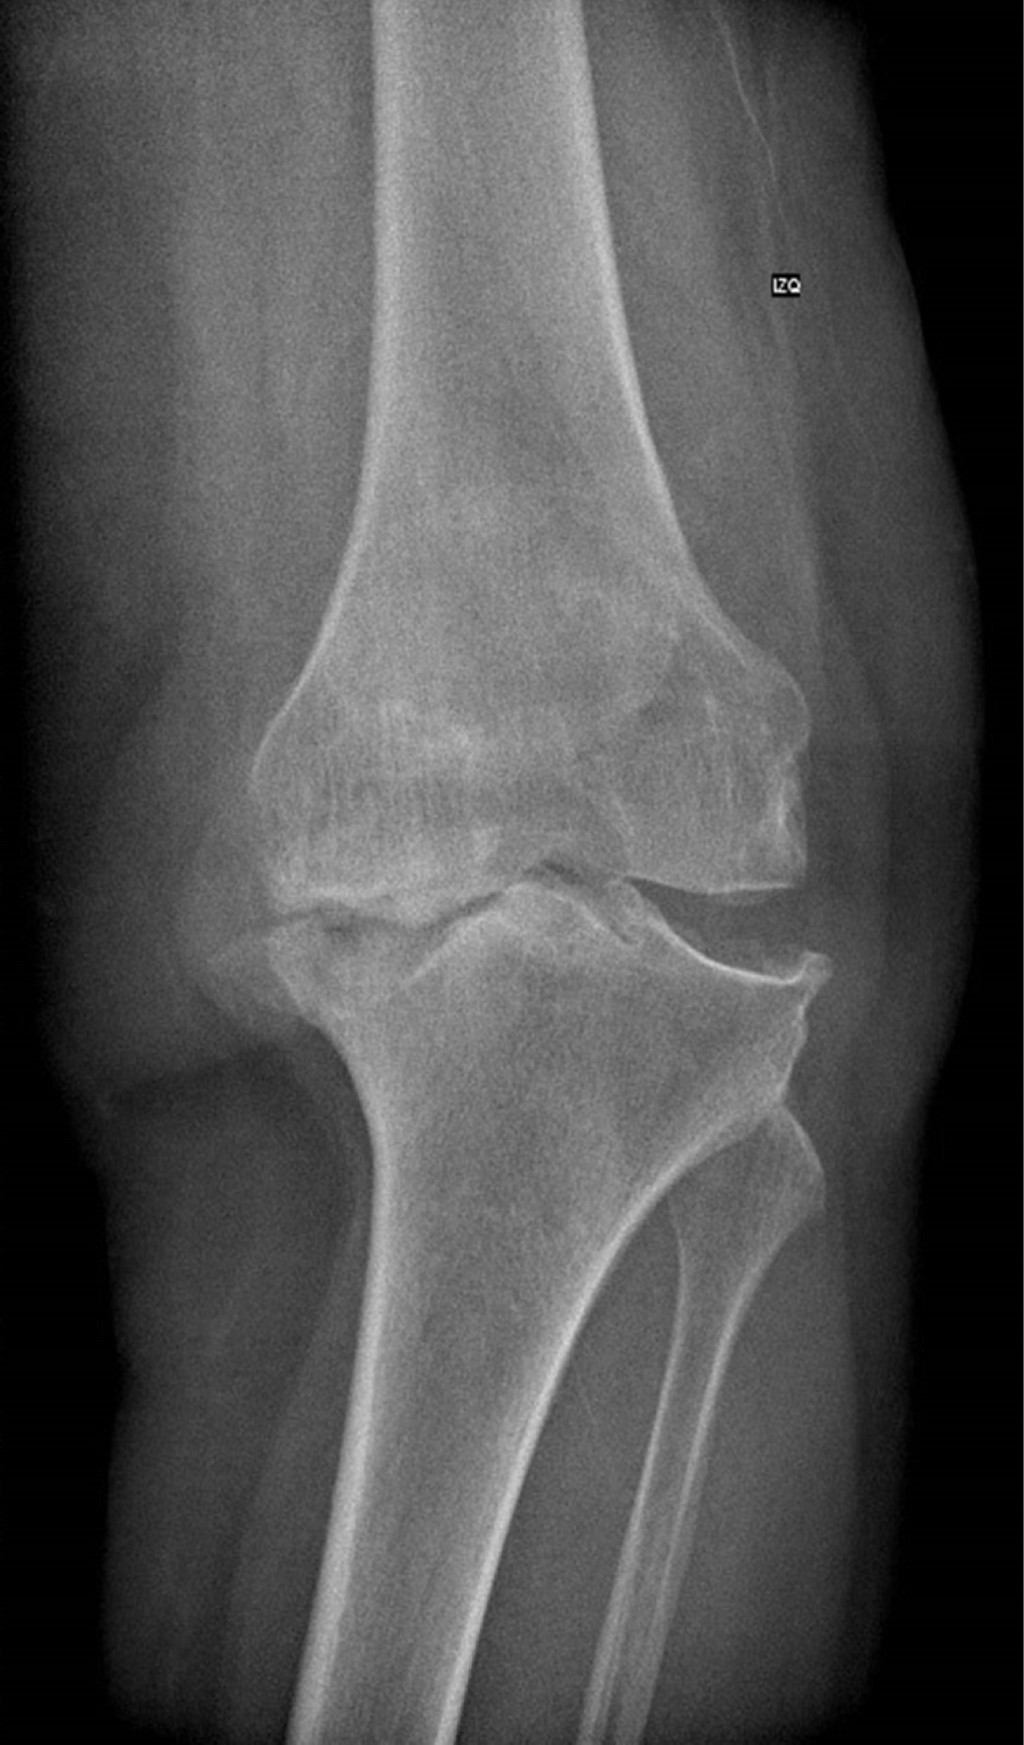

Se presenta caso de mujer de 62 años, dedicada al cuidado del hogar, con antecedente de presbiacusia, la cual acude a consulta externa por gonalgia bilateral, de predominio izquierdo, de siete años de evolución. A la exploración física se aprecia franca deformidad en varo en ambas rodillas (Figura 1), de mayor magnitud en lado izquierdo, con marcha independiente asistida con bastón, rango de movilidad activo con extensión de -5o, flexión de 85o, Ficat y cepillos positivos, cajones negativos y bostezo medial positivo, con limitación por dolor para las actividades de la vida diaria y dolor en EVA de 8. Se solicitan y revisan radiografías anteroposterior (Figura 2) y lateral (Figura 3) de ambas rodillas en bipedestación, encontrando gonartrosis bilateral Kellgreen & Lawrence IV, con defecto tibial medial en rodilla izquierda, por lo cual se le propone tratamiento quirúrgico con artroplastia total de rodilla izquierda posteroestabilizada, debido a la mayor sintomatología en dicho lado.

Figura 1